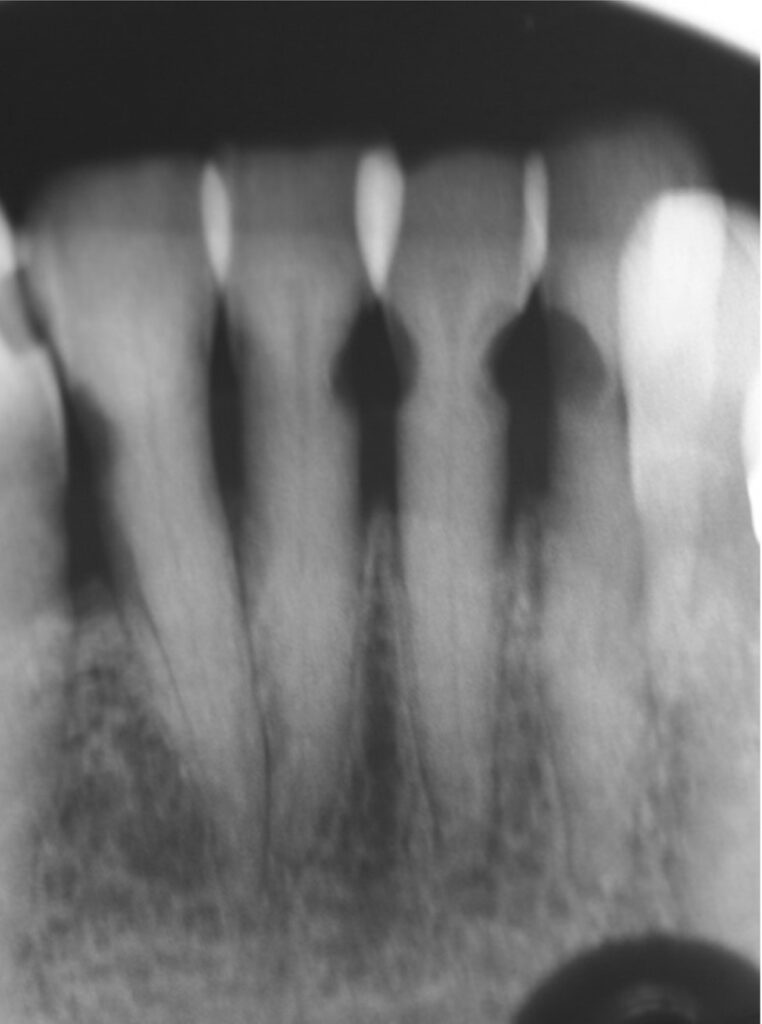

Thứ hai, Fluoride thúc đẩy quá trình tái khoáng hóa tổn thương sâu răng. Fluoride đã được chứng minh là phản ứng với Hydroxyapatite và tạo ra Canxi Fluoride, một nguồn chứa Fluoride và tạo điều kiện cho quá trình tái khoáng hóa sau đó. Một số nghiên cứu đã báo cáo độ cứng vi mô của lớp bề mặt xoang sâu sau khi sử dụng SDF có thể so sánh với ngà răng lành. Trên bề mặt sâu răng bị chặn lại sau khi điều trị bằng SDF, người ta quan sát thấy có vùng tái khoáng cao.

Nhược điểm cố hữu của SDF là các tổn thương sâu răng sẽ bị ố đen sau khi bôi. SDF ngăn chặn sự tiến triển của sâu răng bằng cách hình thành một lớp cứng, đen, không thấm nước trên bề mặt răng và có khả năng chống sâu răng.